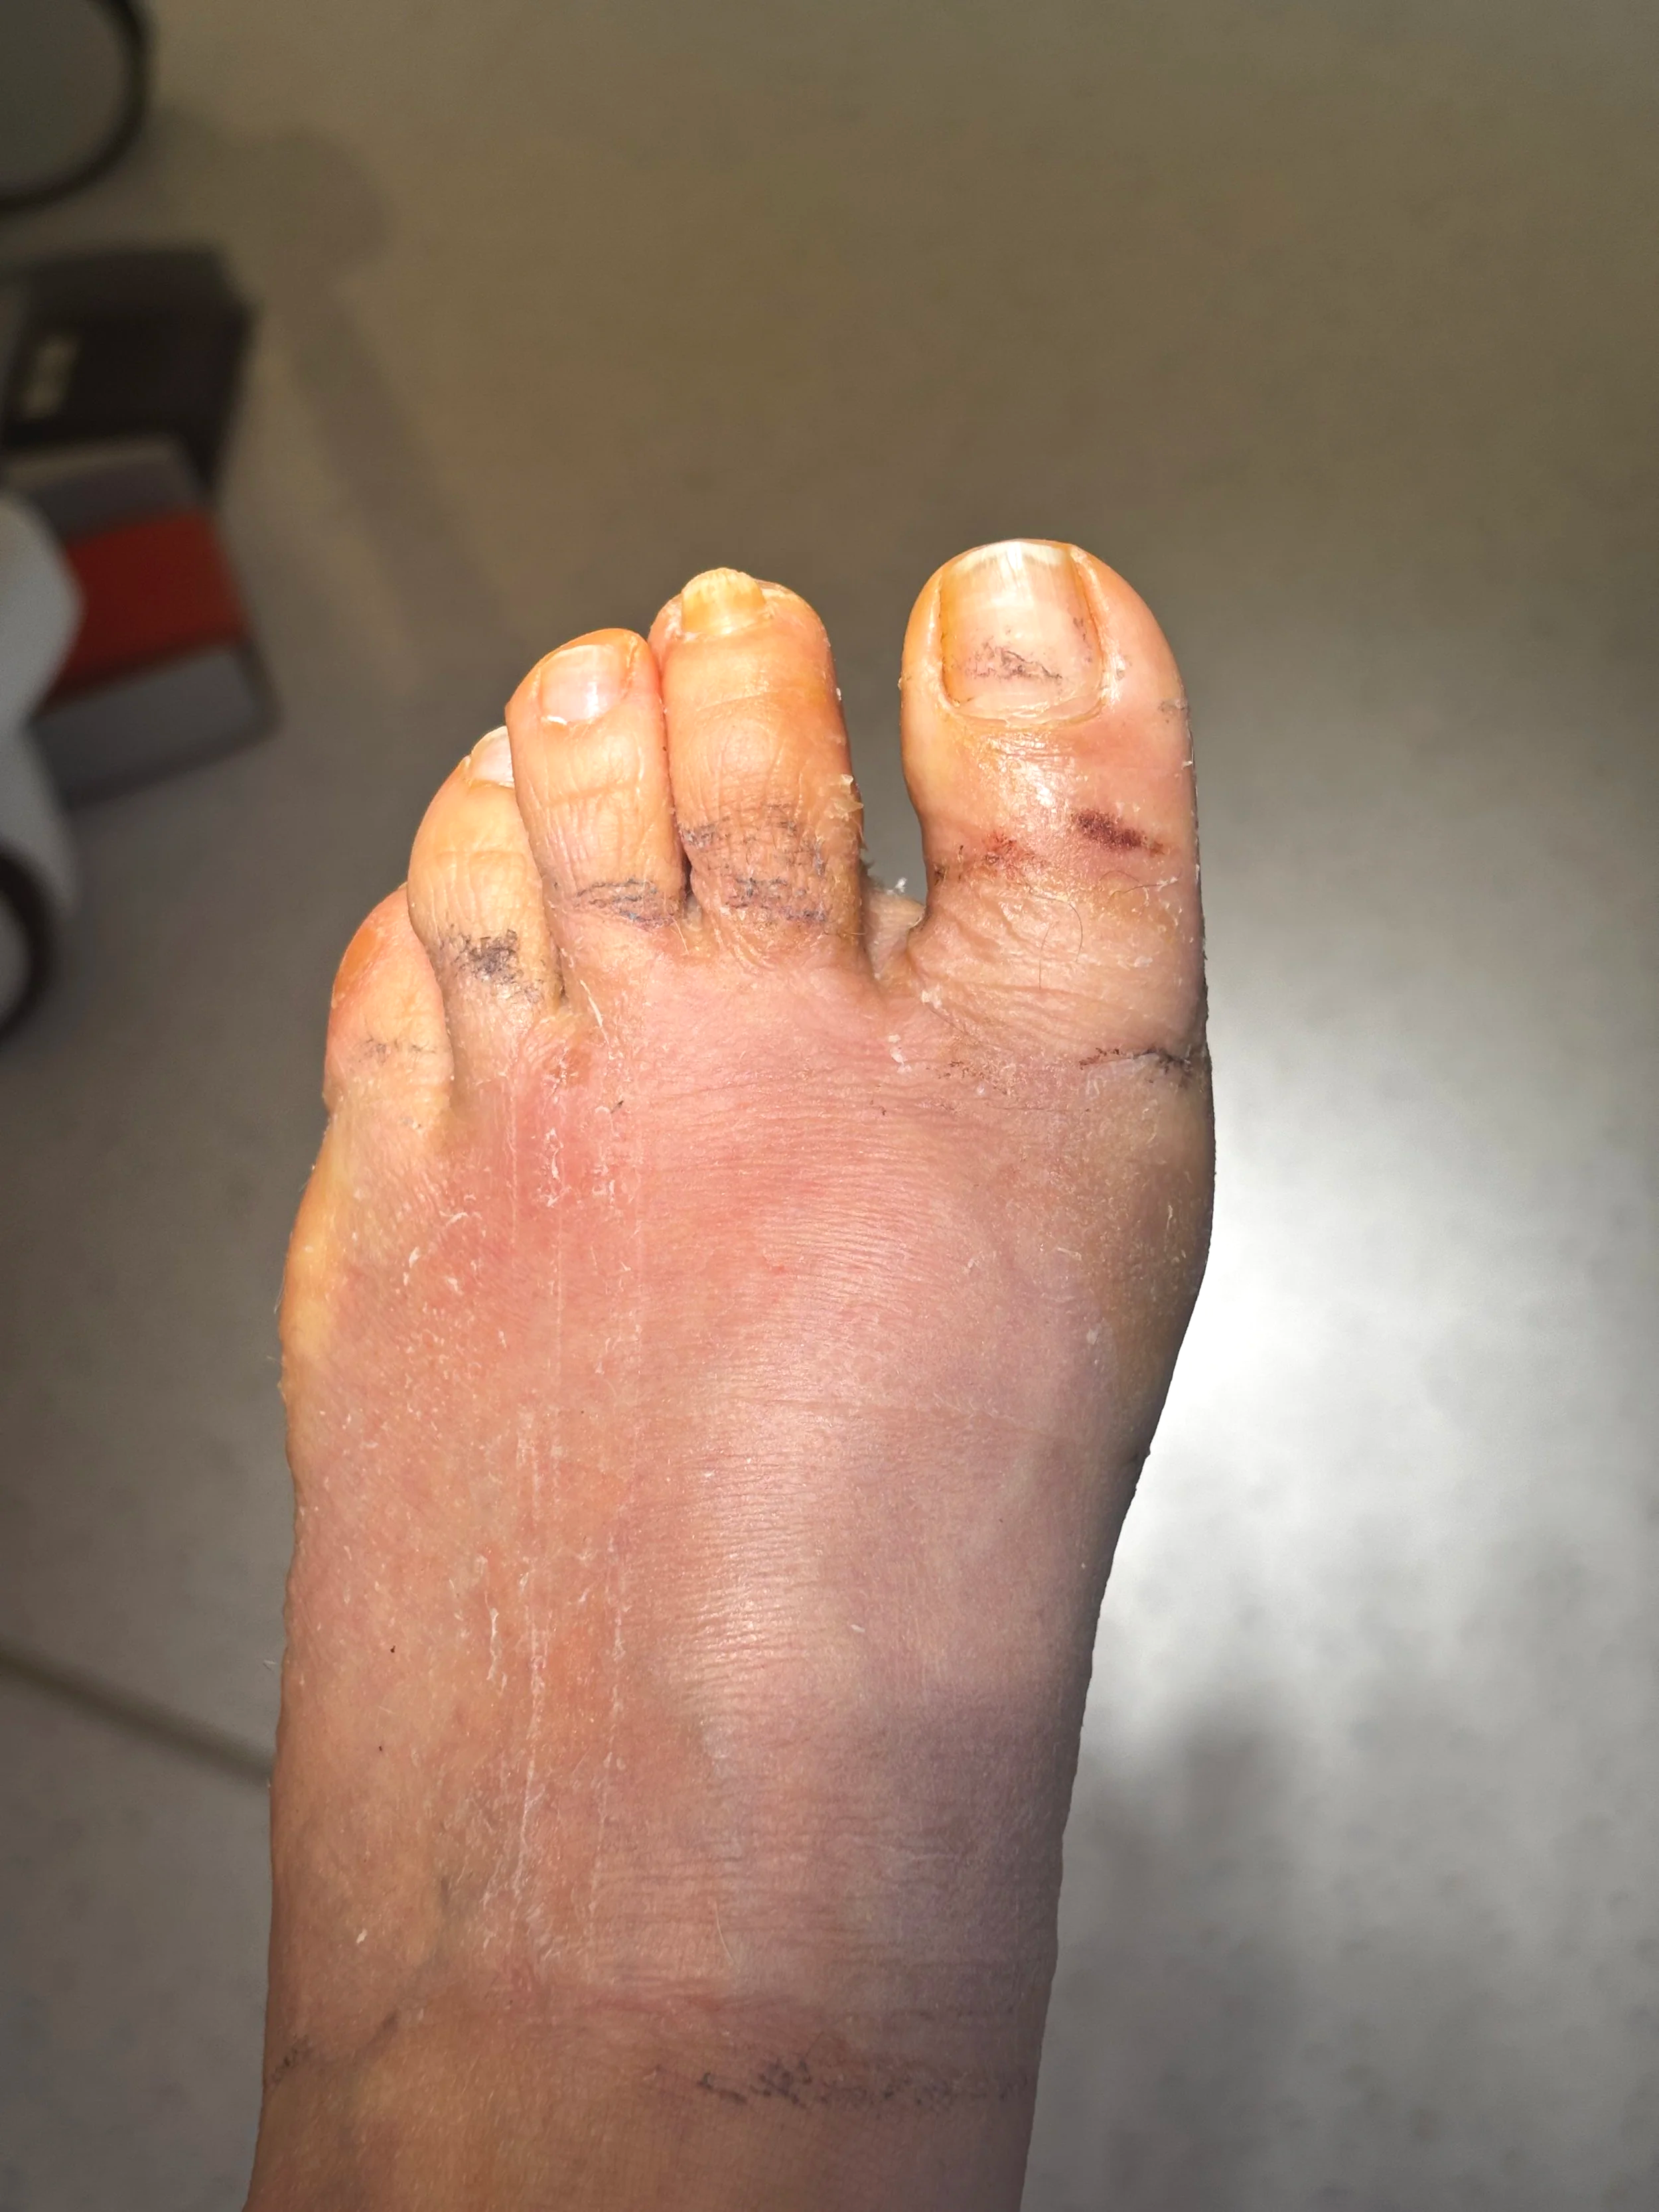

Resultado: antes y después

En estas fotos podemos observar el antes en 1ª y 2ª foto, el día de la intervención 3ª foto, y en el cambio de vendaje de 3ª semana tras intervención.

El resultado muestra no solo una mejora estética, sino también funcional: